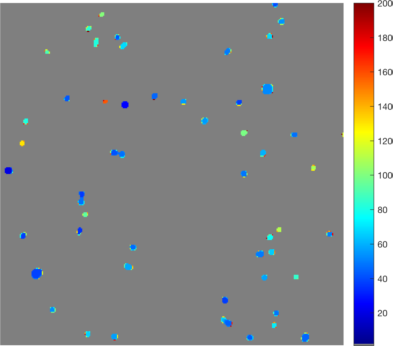

In Figure 14 (a), (d), (g) and (j) experimental data sets are shown. From the original image sets, consisting of three different fluorescent color channels, we extracted the tumor cell marker (green) and used those images as input for our multiscale segmentation approach. Although the difficulties vary between all images (inhomogeneous background, noise, cell clusters, mixture of size and intensity scales), we can process all images with our multiscale segmentation approach with the exact same parameters. This is essential for the development of a user-friendly (parameter-free) toolbox for CTC analysis. Note that the dim spots in image (d) are not cells but only pores of a filter used to collect cells (bright spots) and therefore it is not desired to segment them. The resulting spectral response functions for all four images are shown in Figure 14 (b), (e), (h) and (k) with a color coding corresponding to the coding used in the segmentation results in (c), (f), (i) and (l). The color coding of the response function shows that all objects which appear later in our segmentation and therefore belong to finer scales have a yellow to reddish color in the color-coded segmentation. The very large and intact cells are blue (with some small artifacts at the boundary) and smaller cells (or large fragments) are shown in light blue to green. We can nicely observe that the object colors cover the whole color scale range. For images that are more complex (e.g. (d) and (j)) also the spectral response function is more complex but the color-coded segmentation shows that nearly every object appears in one step and thereby has a clearly defined scale that we use as a feature in our classification approach. Here, we profit from the fact that not only Wulff shapes (perfectly circular objects) but also other eigenshapes appear in one step in our segmentation. Hence, this segmentation approach not only provides all contours automatically without any parameter adaptations but simultaneously also a simple classification of cells based on their size (scale resp. color/appearance time). This analysis can be applied to all color channels separately and be used together with more features in a subsequent automatic classification approach. The constants and can again simply be estimated a-priori from the data by a simple thresholding and averaging approach and are fixed throughout the iterative process.